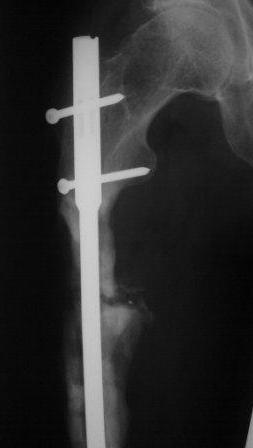

Представляю контрольные послеоперационные рентгенограммы. Во время операции была выделена зона перелома небольшим разрезом, произведена декортикация. Окончательный остеосинтез.